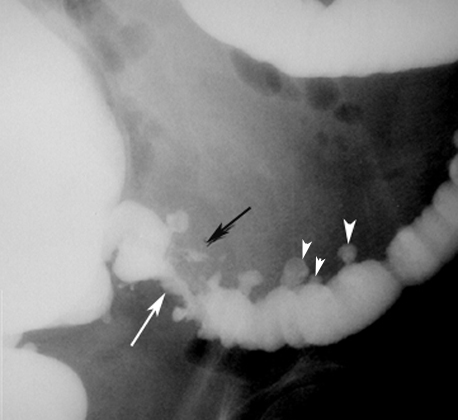

Diverticulitis

CT scan with GI contrast study showing findings of diverticulitis. |

Diverticulitis with Abscess

Findings:

- White arrowheads: Diverticula

- White arrow: Narrowed lumen

- Black arrow: Perforation with intramural abscess